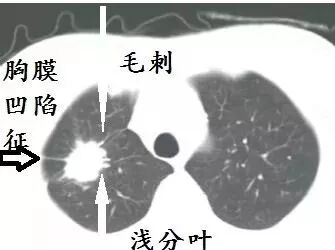

癌,乃魔鬼,张牙舞爪的魔鬼,甚至是吸血鬼。所以,肺癌的CT的特征就是不规则的肿块,有毛刺、分叶,牵拉胸膜引起胸膜凹陷,烂糟糟的空洞,吸血鬼征:血管向肿块聚拢,以供肿瘤吸血。

肿块,结节,在肺部外周,毛刺,分叶,胸膜牵拉,几乎是肺癌,并且,大部分是腺癌,准确性接近90%